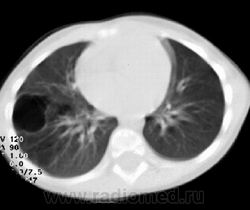

На компьютерных томограммах в заднемедиальном отделе нижней доли левого легкого виден участок повышенной воздушности, легочный рисунок в нем деформирован, не прослеживаются просветы сегментарных бронхов, нет дренирующего бронха.

"Секвестрированный" участок в заднемедиальном отделе нижней доли левого легкого кровоснабжается аномальной артерией, отходящей от аорты.